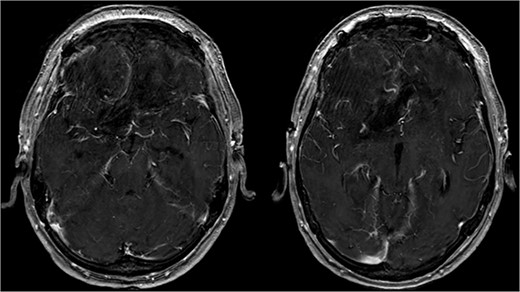

Brain CT imaging unveiled a hypodense fronto-basal lesion measuring 9–10 cm with finger-shaped perifocal edema (Fig. 1). contrast-enhanced cMRI provided more precise dimensions of the lesion (52 x 41 x 82 mm), demonstrating mild compression on both lateral ventricles and posterior displacement of the right middle cerebral artery and both anterior cerebral arteries without signs of hydrocephalus or perfusion disturbances (Fig. 1) and the bilateral COF anastomoses (Fig. 2) .

Showing the CT imaging with a hypodense fronto-basal lesion with finger-shaped perifocal edema and the T1-weighted MRI image with homogenous contrast-enhancing frontobasal lesion demonstrating mild compression on both lateral ventricles and posterior displacement of the right middle cerebral artery (MCA) without evidence of hydrocephalus.

Postoperative cMRI showed typical postoperative changes with no residual tumor tissue (Fig. 4), prompting initiation of extubation and weaning. Histopathological analysis confirmed a meningothelial meningioma (WHO grade I) (Fig. 5) with no indication for further treatment. Discharge occurred after 12 days, with subsequent 6-month follow-up revealing no recurrence and improved cognitive function.

Showing the postoperative T1-weighted MRI with no residual tumor tissue.